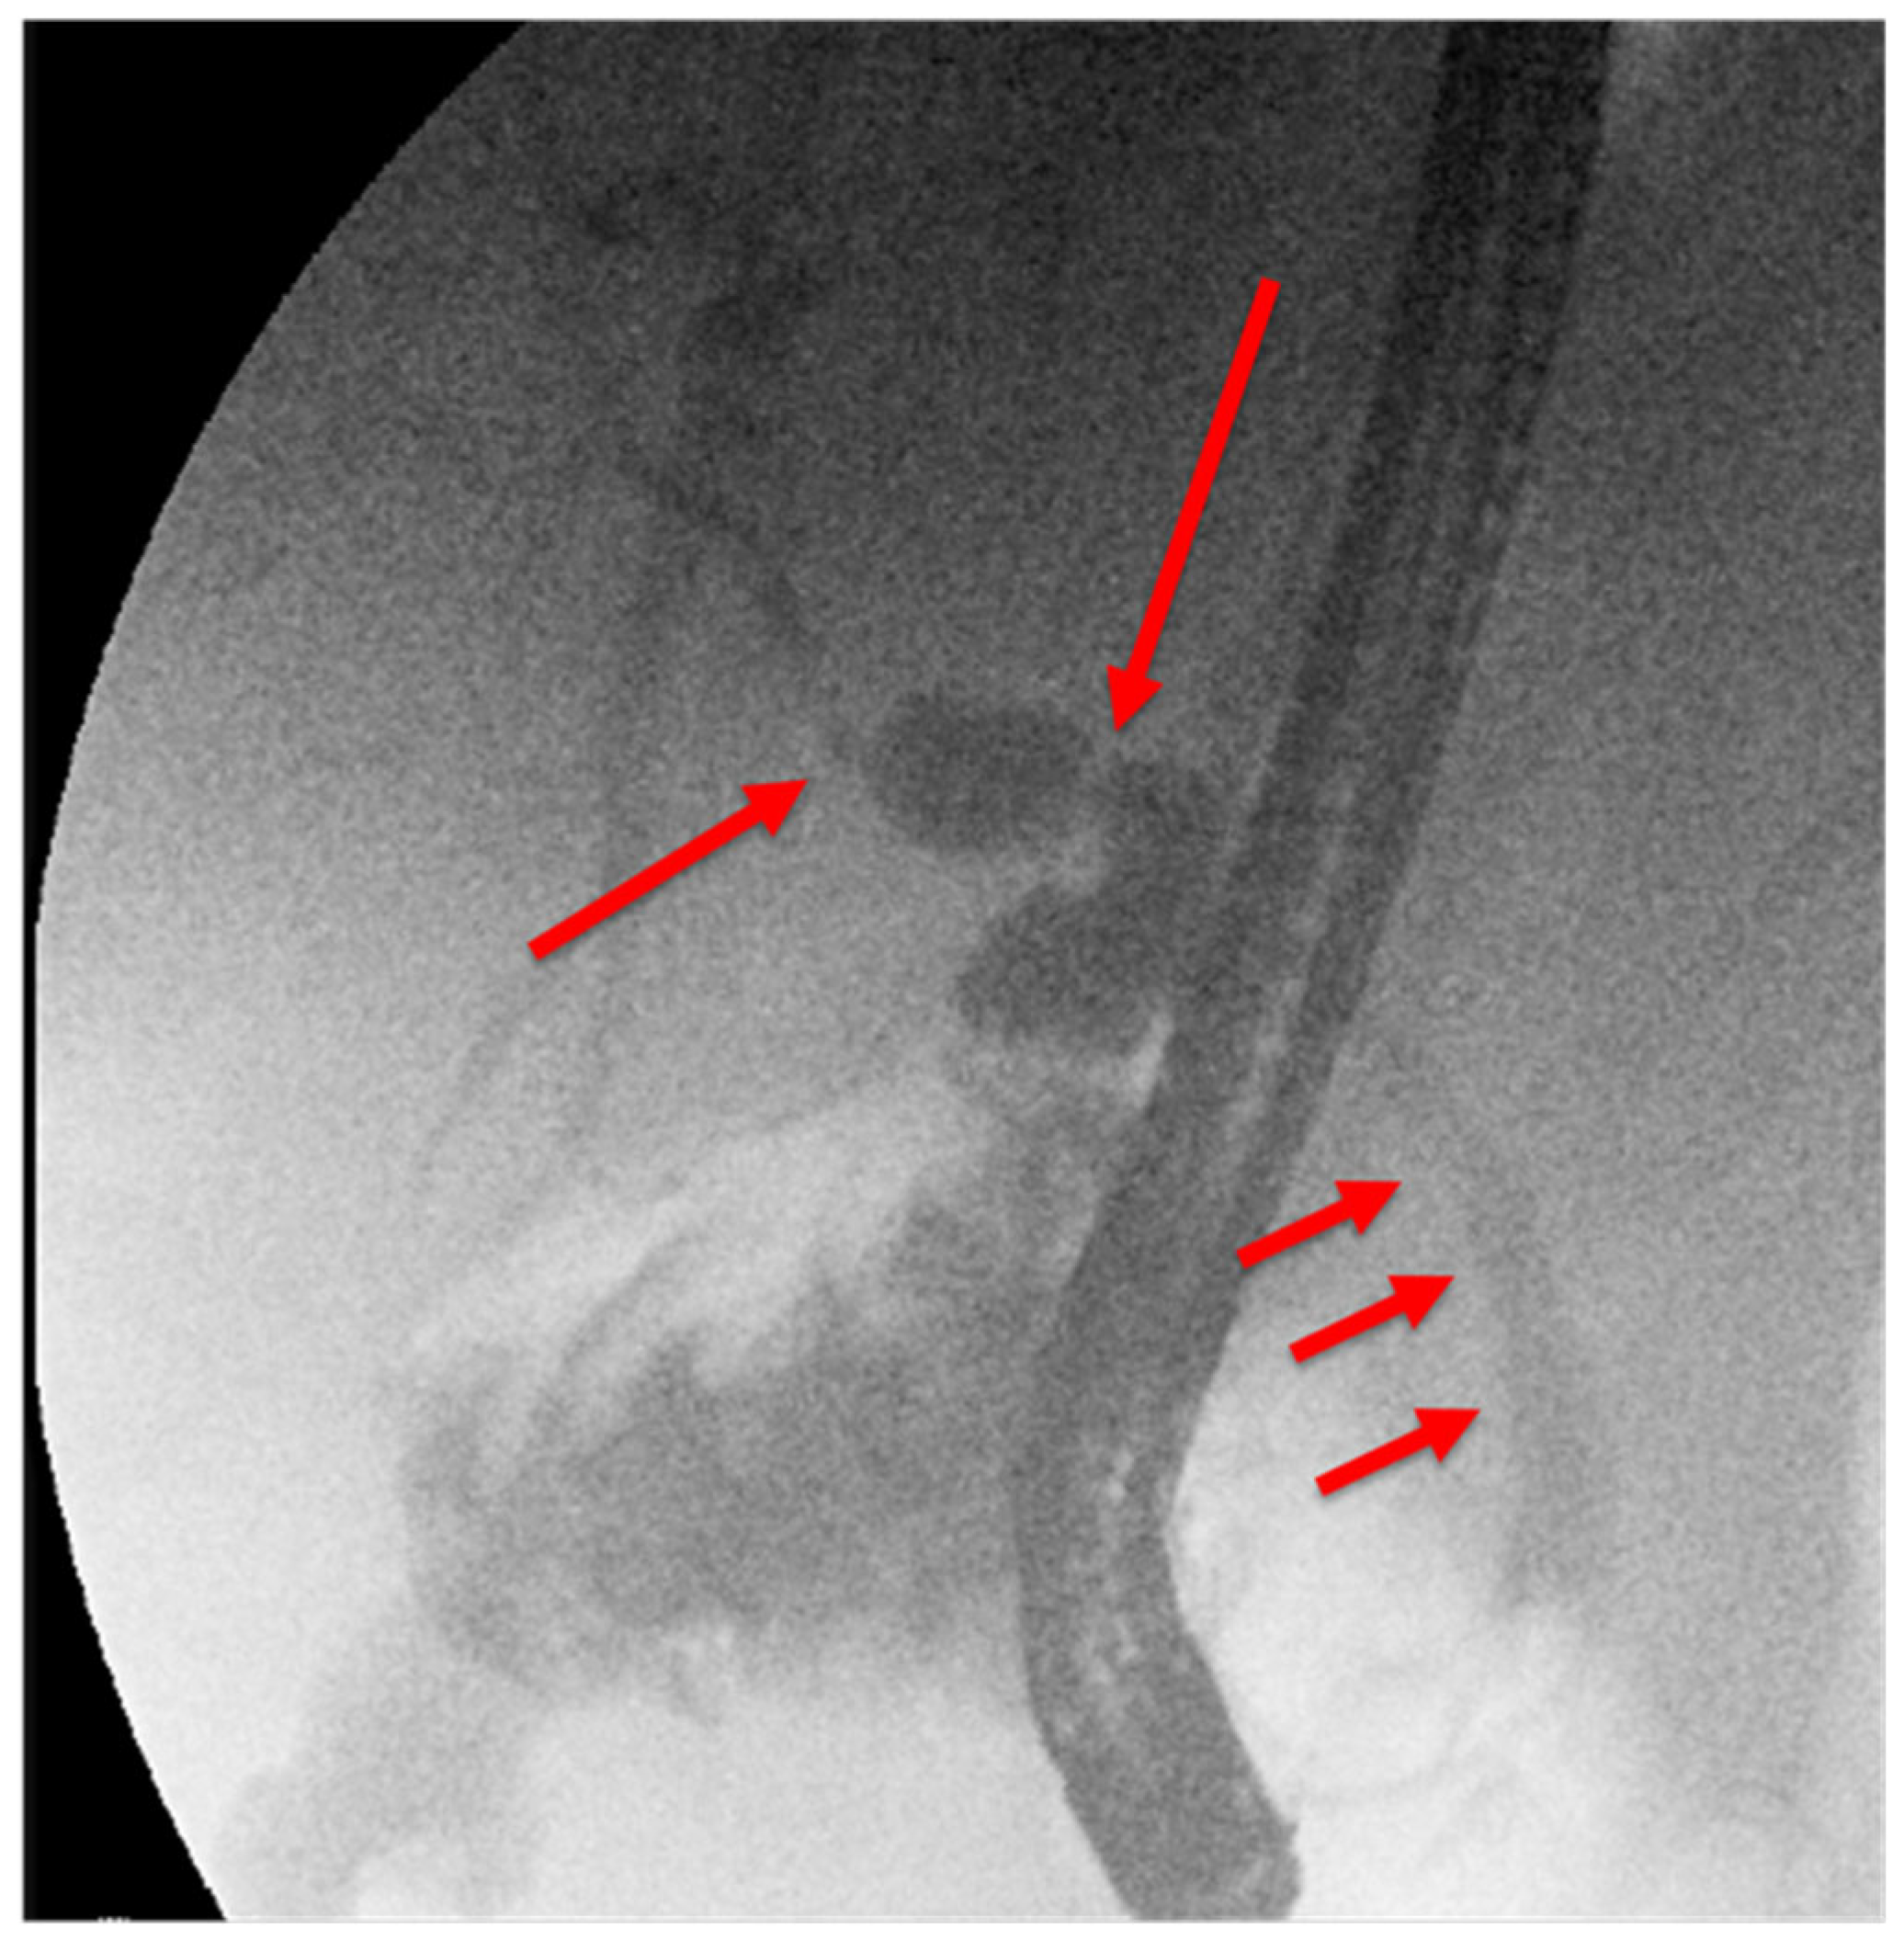

- 18.02: Second ERCP again found no obstructive lesion; a 10Fr/10cm plastic stent was placed empirically (Figure 2B). No clinical or biochemical improvement was observed.

- 14.02: First ERCP showed normal bile ducts and papilla, no strictures or filling defects (Figure 2A).